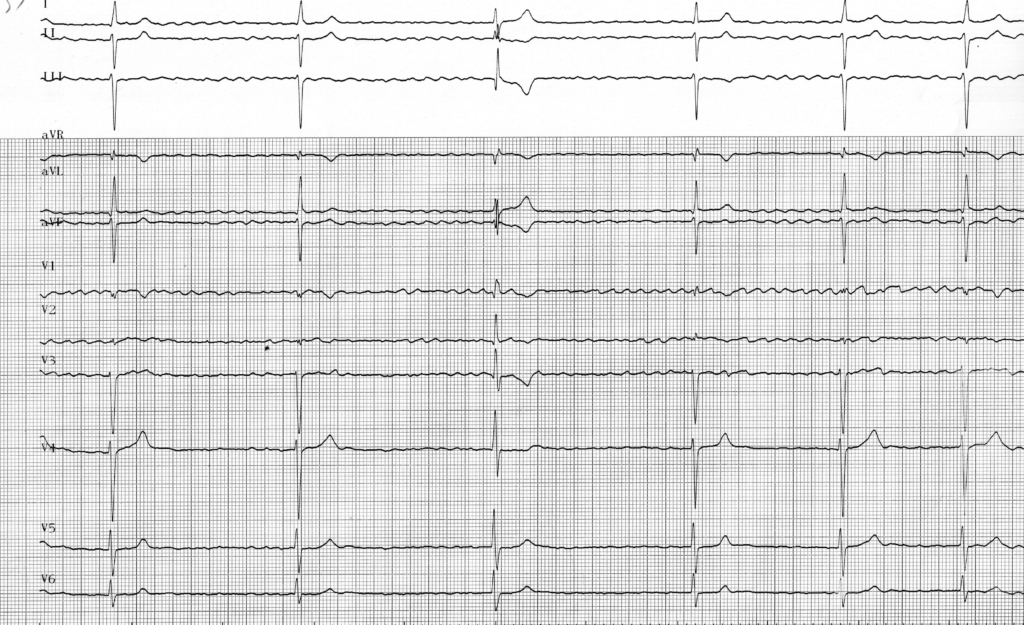

Tracé 1.11: Fibrillation atriale et trouble de conduction atrioventriculaire

Homme de 83 ans; hospitalisation pour syncope

FA: activité atriale très rapide, polymorphe, anarchique avec trémulation de la ligne de base; FA lente correspondant à une FA conduite (ventricules fins irréguliers) mais avec une conduction atrio-ventriculaire altérée (ventricules très lents); le troisième complexe correspond probablement à un échappement jonctionnel (QRS fin avec un aspect légèrement différent par rapport aux QRS conduits);

Ce patient présente donc une FA lente. Lors d’un épisode de FA en présence d’une conduction atrio-ventriculaire préservée, le rythme ventriculaire est irrégulier, rapide et supérieur à 100 bpm même si il reste bien inférieur à celui des oreillettes. Il existe en effet un “bloc” fonctionnel au niveau de la jonction en raison de la durée de la période réfractaire du nœud auriculo-ventriculaire. Il existe toutefois certaines particularités à connaitre. La fréquence ventriculaire peut être très ralentie comme chez ce patient avec un rythme pouvant être inférieur à 40 bpm. Une bradycardie ventriculaire régulière suggère l’existence d’un BAV complet avec interruption totale de la conduction et échappement le plus souvent jonctionnel. Un rythme ventriculaire restant irrégulier est plutôt en faveur d’une conduction très altérée mais toujours présente.

Dans les 2 cas, quand le patient est symptomatique sur une fréquence ventriculaire très lente, l’indication d’implantation d’un stimulateur cardiaque est indiscutable.

Le diagnostic de fibrillation auriculaire doit être porté sur la mise en évidence d’une activité atriale, irrégulière, anarchique et très rapide. L’existence d’une fréquence ventriculaire rapide et irrégulière est fréquente mais n’est pas un prérequis au diagnostic. En effet, comme chez ce patient, la fréquence ventriculaire peut être lente et plus ou moins régulière en présence d’un trouble de conduction auriculo-ventriculaire.